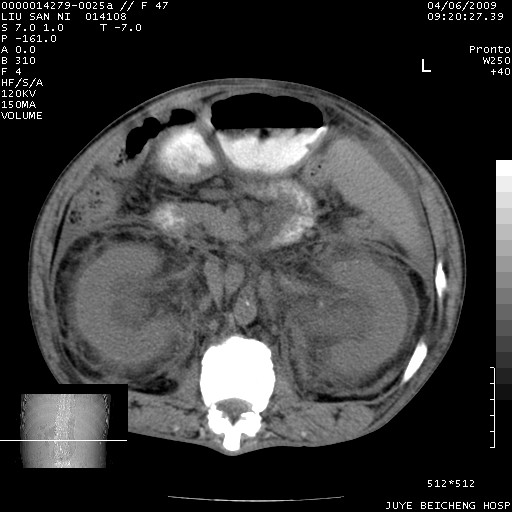

以下是引用前行在2009-4-7 10:31:00的发言:[br]肝脾肿大;双肾增大,双肾盂少量积水可能,肾膜膜增厚,肾周间隙增宽,并见桥间隔,提示结缔组系统疾病、系统性红瘢狼疮肾可能性大。继发右侧胸腔、心包、腹腔积液。

以下是引用深泽交通医院在2009-4-7 11:21:00的发言:[br]双侧肾周密度增高,见条索影,右肾实质见点片状低密度区,考虑弥漫肾炎【自身免疫性?】;;肾性水肿征